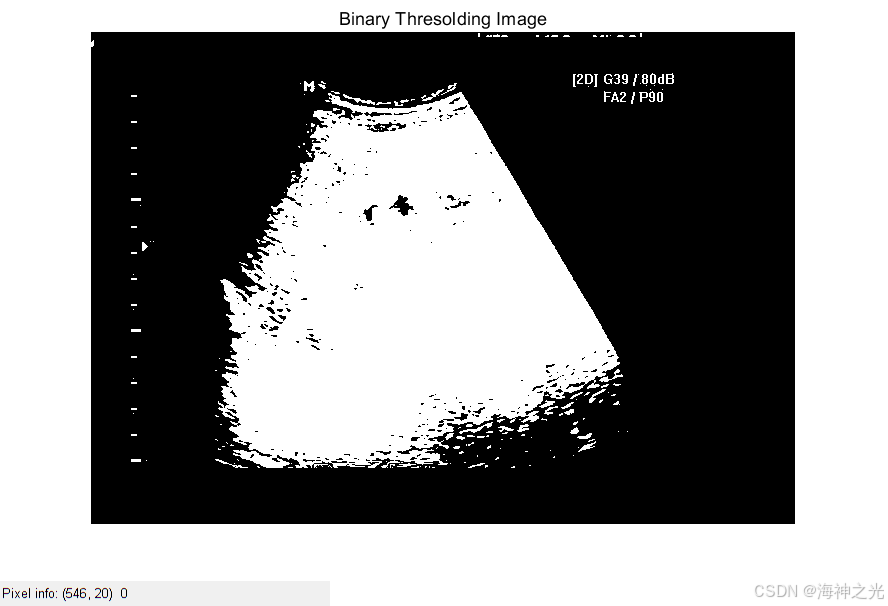

⛄三、运行结果

[1]庄健,杨晔,潘希德.一种针对超声检测图像的自适应阈值设置方法[J].西安交通大学学报. 2015